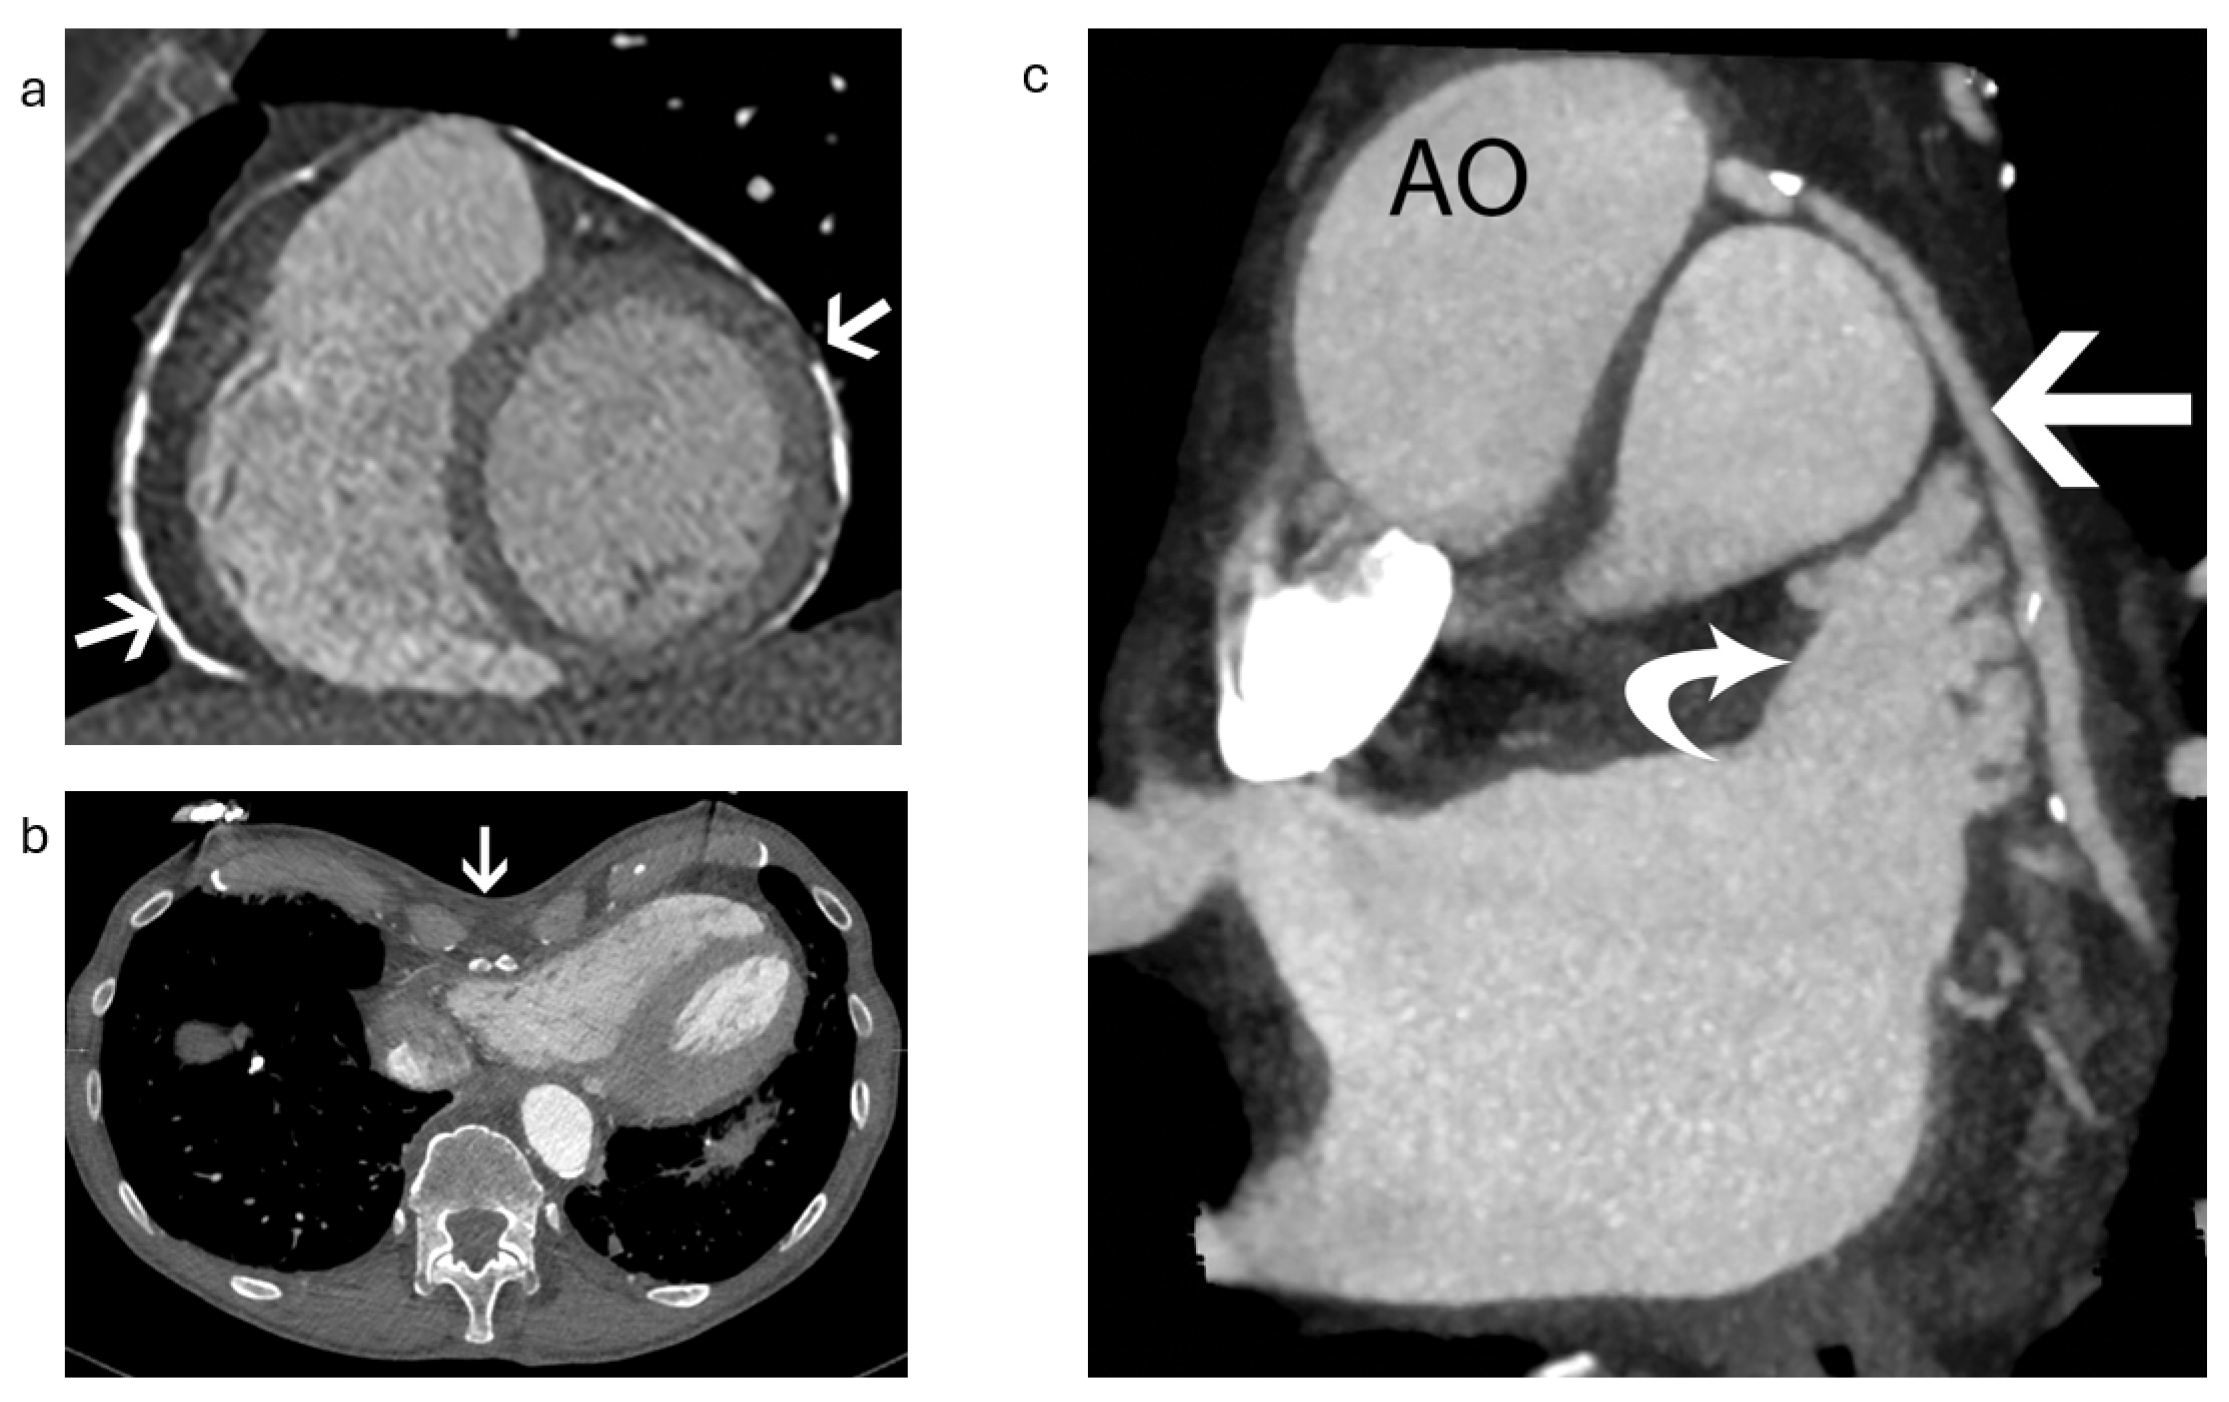

2.1.1. Anatomical Contraindications

2.1.2. LAA Measurements

- Romero, J.; Husain, S.A.; Kelesidis, I.; Sanz, J.; Medina, H.M.; Garcia, M.J. Detection of Left Atrial Appendage Thrombus by Cardiac Computed Tomography in Patients with Atrial Fibrillation: A Meta-Analysis. Circ. Cardiovasc. Imaging 2013, 6, 185–194. [Google Scholar] [CrossRef] [PubMed]